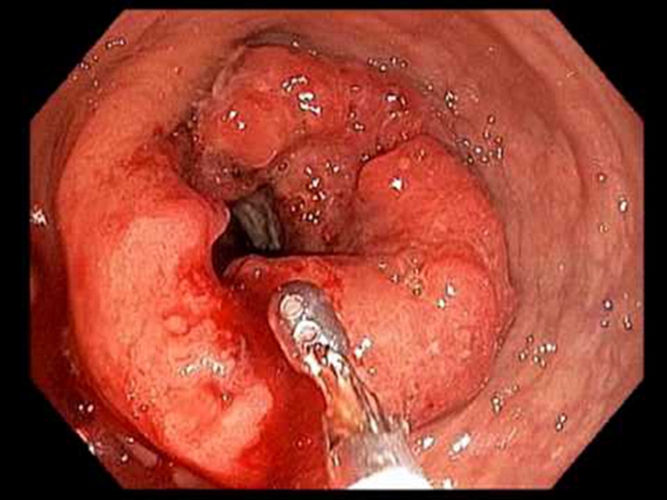

右半結腸癌腺癌